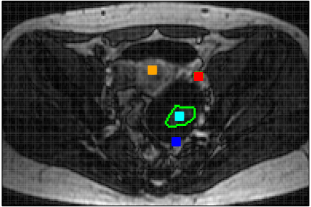

The real DCE-MR image sequences of two female pelvis with ovarian tumors [Thomassin-Naggara et al., 2012] consist of, respectively, 130 and 107 images on a grid of 192x128 voxels, acquired over 305 seconds, see Figure 3. With the delayed injection of the contrast agent bolus, their ( and 10) first images show only the grey level baseline up to the noise level. In both sequences, a ROI around the tumor has been manually drawn by an experienced radiologist after acquisition.

The two real DCE-MR image sequences have been fully segmented into homogeneous regions that are highly consistent with anatomical structures as shown in Figure 13. The smaller is, the more details in anatomical structures can be observed in image sequence. This is highlighted (see Fig. 14) in the ROIs defined by the squares that contain the manually segmented ROIs, shown in black on Figure 13. The corresponding estimated TCs inside each cluster within the ROI together with their corresponding size are shown in Figure 15. By segmenting the full DCE sequence, these estimated TCs are obtained by averaging TCs which do not necessarily belong to the ROI but do belong to the same homogeneous cluster. As a benefit, the SNR observed for these estimated TCs is strongly improved, providing a real opportunity for further analysis and comparisons. From these figures, one can clearly understand the advantages of DCE-HiSET. It is indeed providing a piecewise constant representation of the DCE image sequence in functionally homogeneous regions, where controls the size of the pieces and the functional discrepancy between them.

Patient 1

Patient 2